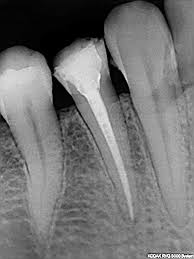

To understand a root canal procedure, it helps to know about the anatomy of the tooth. Inside the tooth, under the white enamel and a hard layer called the dentin, is a soft tissue called the pulp. The pulp contains blood vessels, nerves and connective tissue, and helps to grow the root of your tooth during development. In a fully developed tooth, the tooth can survive without the pulp because the tooth continues to be nourished by the tissues surrounding it.

The pulp is the living tissue of the tooth with blood supply and nerve supply. Once the dental caries (decay) involves the pulp, the pulp gets infected causing pain. The aim of the root canal treatment is to remove the infected pulp. This is done by removing the infected pulp with files in the pulp chamber and cleaning and shaping the root canals and sealing the canal with a filling material.